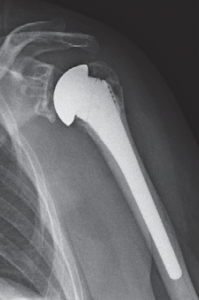

Schultergelenksprothesen gibt es seit über 50 Jahren. Gerade in den letzten 20 Jahren hat die Schulterendoprothetik große Fortschritte gemacht. Bei der schmerzhaften Zerstörung des Schultergelenkes durch Arthrose (Gelenkverschleiß), rheumatoide Arthritis (rheumatische Gelenkentzündung), Oberarmkopfnekrose (Absterben des Oberarmkopfes) oder Oberarmkopfbruch ist es heute mit gutem Erfolg möglich, die Gelenkflächen von Oberarmkopf und Schulterpfanne durch Prothesen aus Titan und Polyethylen zu ersetzen. Die Indikation zur Implantation einer Schultergelenksprothese wird gestellt bei:

Oberarmkopfnekrose

Durch Medikamente (z.B. Cortison), übermäßigen Alkoholgenuss, als Unfallfolge oder andere noch nicht bekannte Ursachen kann es zu einer Minderdurchblutung des Oberarmkopfes kommen. Dies hat ein Absterben der Knochenzellen zur Folge, das zu einer Deformierung des Oberarmkopfes mit schmerzhafter Bewegungseinschränkung führt. Bei dieser Erkrankung reicht bei frühzeitigem Eingreifen eine Oberarmkopfprothese aus (Abb. 44a, b). Erst wenn durch die Inkongruenz der Gelenkflächen auch die Gelenkpfanne mitbetroffen ist, muss eine zusätzliche Pfannenkomponente implantiert werden.